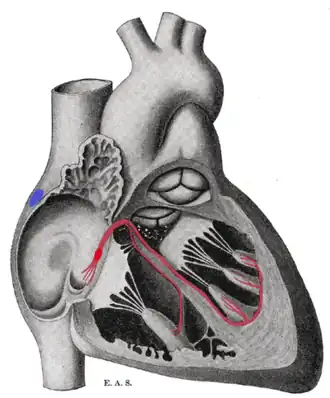

AV Bundle

The bundle of HIS is a collection of heart muscle cells specialized for electrical conduction that transmits the electrical impulses from the AV node (located between the atria and the ventricles) to the point of the apex of the fascicular branches. The fascicular branches then lead to the Purkinje fibers which innervate the ventricles, causing the cardiac muscle of the ventricles to contract at a paced interval. These specialized muscle fibers in the heart were named after the Swiss cardiologist Wilhelm His, Jr., who discovered them in 1893. Cardiac muscle is very specialized, as it is the only type of muscle that has an internal rhythm; i.e., it is myogenic which means that it can naturally contract and relax without receiving electrical impulses from nerves. When a cell of cardiac muscle is placed next to another, they will beat in unison. The fibers of the Bundle of HIS allow electrical conduction to occur more easily and quickly than typical cardiac muscle. They are an important part of the electrical conduction system of the heart as they transmit the impulse from the AV node (the ventricular pacemaker) to the rest of the heart. The bundle of HIS branches into the three bundle branches: the right left anterior and left posterior bundle branches that run along the intraventricular septum. The bundles give rise to thin filaments known as Purkinje fibers. These fibers distribute the impulse to the ventricular muscle. Together, the bundle branches and purkinje network comprise the ventricular conduction system. It takes about 0.03-0.04s for the impulse to travel from the bundle of HIS to the ventricular muscle. It is extremely important for these nodes to exist as they ensure the correct control and co-ordination of the heart and cardiac cycle and make sure all the contractions remain within the correct sequence and in sync.